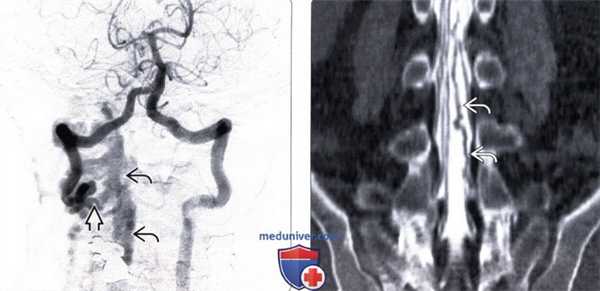

(Справа) Сагиттальный срез, FS Т1-ВИ с КУ: классическая картина контрастного усиления сигнала спинного мозга с нечеткими границами, диффузного характера, без четкого разделения с окружающей паренхимой спинного мозга. (Слева) На фронтальной реконструкции динамической контрастной МР-ангиографии на поверхности спинного мозга видны патологические сосуды, а слева на уровне T9 достаточно четко определяется фистула, выглядящая как более компактное сосудистое образование в области неврального отверстия.

(Справа) На катетерной ангиограмме после контрастирования левой межреберной артерии T9 на уровне неврального отверстия видна фистула 1 типа, обеспечивающая сброс крови в расширенные вены фронтального венозного сплетения. (Слева) Сагиттальный срез, Т2-ВИ: расширенные дренирующие вены определяются в виде множественных сосудистых пустот, расположенных вокруг спинного мозга. Зона гиперинтенсивного Т2-сигнала спинного мозга в краниальном и каудальном направлении конусовидно сужается, периферическая паренхима спинного мозга при этом выглядит нормально, что типично для венозного гипертензивного отека.

(Справа) На катетерной ангиограмме отмечается шунтирование крови контраста через фистулу 7 типа в окружающее спинной мозг венозное сплетение. (Слева) Сагиттальный срез, Т1-ВИ с КУ: диффузное контрастное усиление сигнала спинного мозга от уровня шей но- медуллярного перехода до С5. Картина напоминает спинальную дуральную фистулу 1 типа, однако причиной миелопатии в данном случае стала фистула задней черепной ямки со сбросом крови в интраспинальное венозное сплетение.

(Справа) Ангиография: после контрастирования левой позвоночной артерии в венозную фазу визуализирована дуральная фистула задней черепной ямки (5 тип по Cognard), кровоснабжаемая менингеальными ветвями и шунтирующая кровь в интраспинальные венозные сплетения вдоль дорзальной и вентральной поверхности спинного мозга, напоминающая тем самым спинальную дуральную фистулу 7 типа.д) Клинические особенности:

(Слева) На парасагиттальном Т1-ВИ пациента с переломом С2 определяется расширение вентрального эпидурального венозного сплетения с выраженным сигналом потока крови.

(Слева) На цифровой ангиограмме, выполненной через левую позвоночную артерию, отмечается наличие высокопоточного артериовенозного шунта в области V2/V3 перехода правой позвоночной артерии с формированием обратного кровотока в дистальном отделе правой позвоночной артерии, кровоснабжающей расширенное эпидуральное венозное сплетение и расширенные глубокие шейные вены.

(Справа) КТ-миелограмма, фронтальная проекция поясничного отдела позвоночника: расширение и извитость вен каудального отдела дурального мешка связанные с формированием посттравматической (ятрогенной) артериовенозной фистулы.1. Клиническая картина травматической артериовенозной фистулы позвоночника: